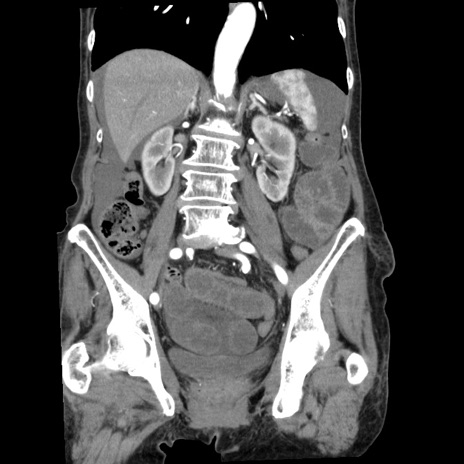

症例1(冠状断像)

【症例】80歳代女性

【主訴】腹痛

【現病歴】8時間前から腹痛あり来院。

【既往歴】糖尿病、脂質異常症、子宮体癌にて子宮全摘術

【身体所見】意識清明・会話良好だが腹痛で苦悶様、全腹部にわたって反跳痛と圧痛あり

【データ】WBC 13600、CRP 0.14、LDH 224、CK 90